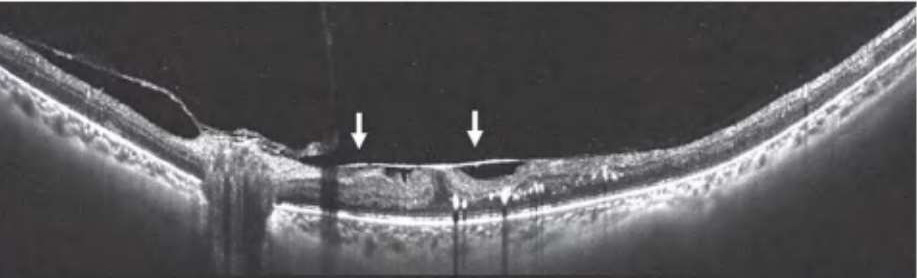

图2-2-1 抗VEGF及PRP治疗后玻璃体后脱离范围显著扩大的PDR案例

A.PDR合并玻璃体视网膜牵拉引发的相关DME,既往已行PRP,行4次抗VEGF药物治疗后,黄斑区玻璃体后界膜与视网膜分离(白色箭头所示),玻璃体视网膜牵拉解除,黄斑水肿较前明显好转。B.PDR合并玻璃体视网膜牵拉性相关DME,在行3次视网膜激光光凝治疗后,黄斑区玻璃体后界膜与视网膜分离(白色箭头所示),玻璃体视网膜牵拉缓解,黄斑水肿较前好转。